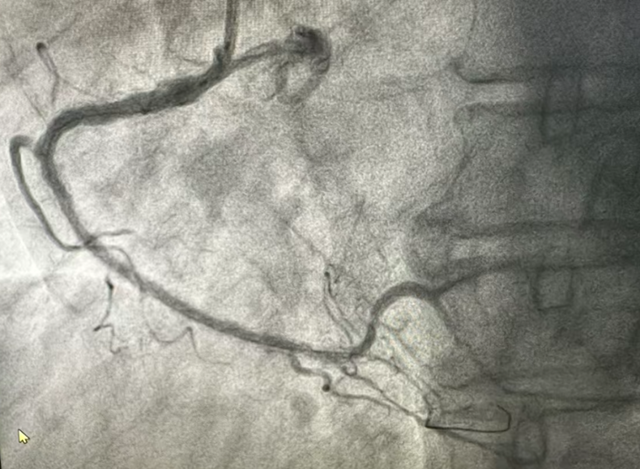

术后患者胸痛、憋气等症状显著缓解,血流动力学趋于稳定。此次从药物溶栓到择期介入的序贯治疗,不仅及时挽救了心肌,也为患者后续的系统治疗与心脏康复奠定了关键基础。

完善造影显示右冠支架内血流通畅: